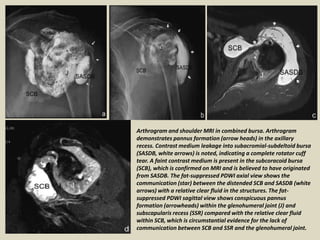

Arthrogram and shoulder MRI in combined bursa. Arthrogram

demonstrates pannus formation (arrow heads) in the axillary

recess. Contrast medium leakage into subacromial-subdeltoid bursa

(SASDB, white arrows) is noted, indicating a complete rotator cuff

tear. A faint contrast medium is present in the subcoracoid bursa

(SCB), which is confirmed on MRI and is believed to have originated

from SASDB. The fat-suppressed PDWI axial view shows the

communication (star) between the distended SCB and SASDB (white

arrows) with a relative clear fluid in the structures. The fat-

suppressed PDWI sagittal view shows conspicuous pannus

formation (arrowheads) within the glenohumeral joint (J) and

subscapularis recess (SSR) compared with the relative clear fluid

within SCB, which is circumstantial evidence for the lack of

communication between SCB and SSR and the glenohumeral joint.